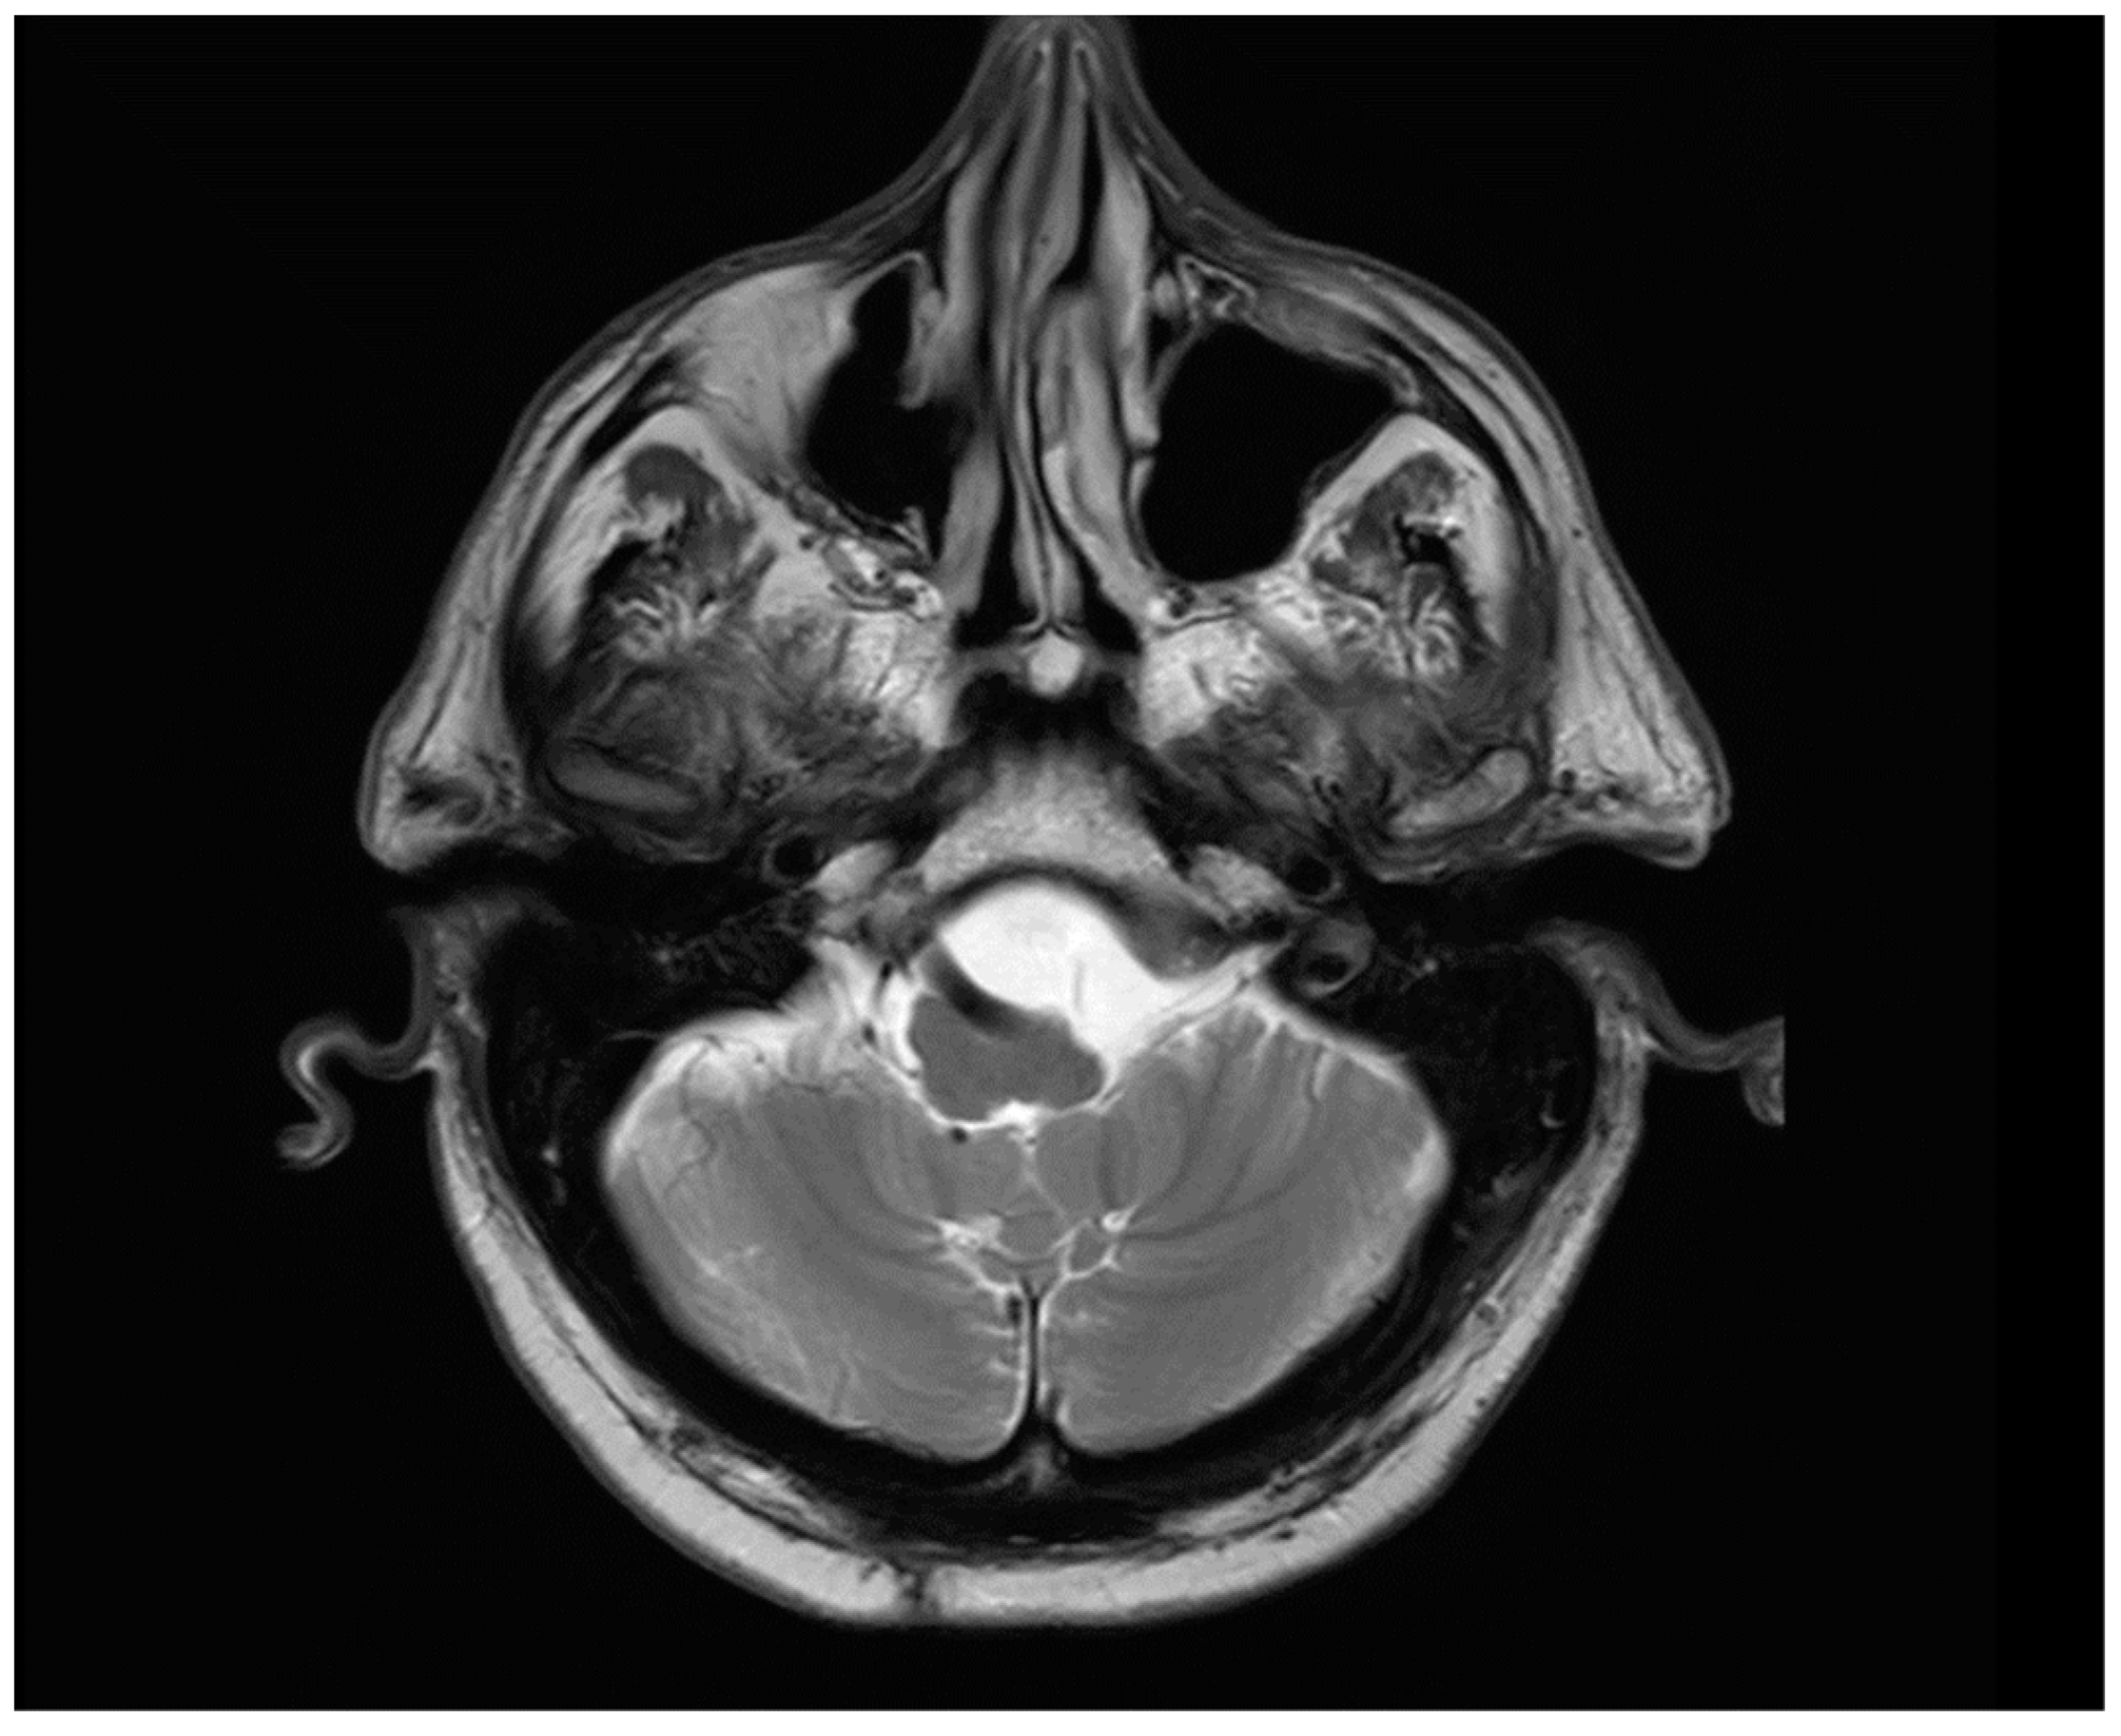

2. Presentation